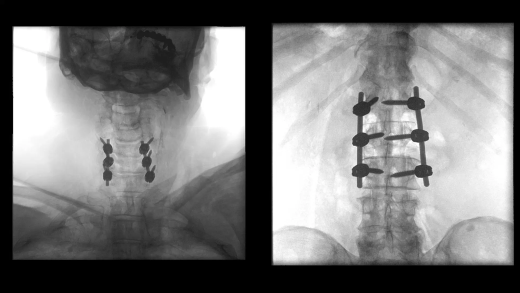

- Улучшенная цепочка визуализации матричного детектора с технологией CMOS: интеллектуальные алгоритмы автоматически регулируют яркость и контрастность, обнаруживают движение, улучшают края и оптимизируют визуализацию металла для улучшения изображения окружающих тканей

- SpotAdapt и сенсорные жесты: SpotAdapt автоматически оптимизирует параметры визуализации в соответствии с интересующей анатомией. Сенсорные жесты, как на планшете, позволяют коллимировать, поворачивать и переворачивать изображения, а также использовать преимущества SpotAdapt всего одним пальцем.

Больницы сталкиваются с ростом стоимости медицинского оборудования, поэтому им необходимо оправдать инвестиции. Cios Flow — это многофункциональная система, которую можно использовать в различных областях — ортопедической и травматологической хирургии, хирургии позвоночника, сосудистой хирургии и т. д. — позволяя повысить эффективность использования своих ресурсов.